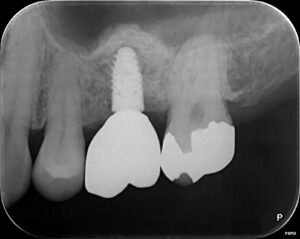

左上6番目の歯が割れてしまい、インプラントを行いました!!

骨が少かったため再生療法を行い、インプラントを埋入しました💡

術後は噛めるようになったこと、大変綺麗な仕上がりで

満足されておりました😊

【✨術後✨】